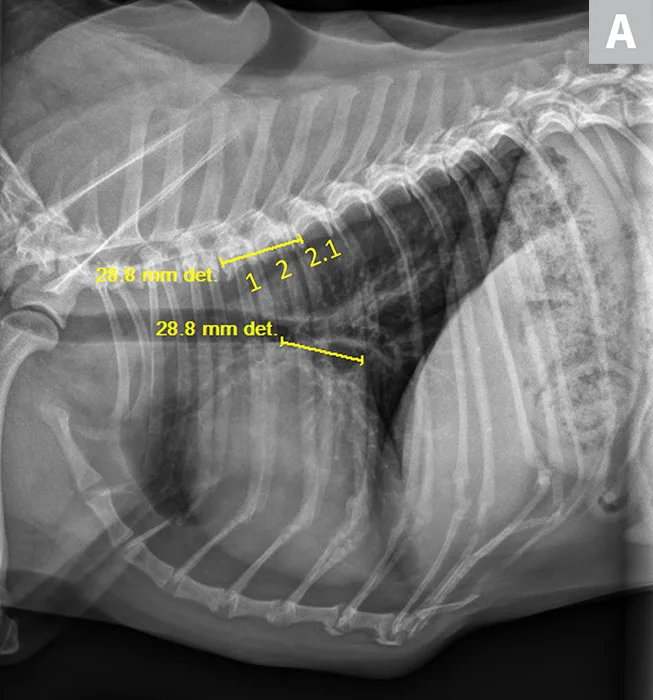

FIGURE 1

VLAS measurement in a dog with suspected stage B1 MMVD using a left lateral radiograph (A). A caliper was used to measure from the center of the most ventral aspect of the carina to the most caudal aspect of the left atrium, where it intersects with the dorsal border of the caudal vena cava. This measurement was transferred to the cranial aspect of T4 and extended caudally along the thoracic vertebrae. The number of vertebrae this line transversed was rounded to the nearest tenth to determine VLAS (2.1 VBUs). Stage B1 MMVD was confirmed via echocardiography. A redundant dorsal tracheal membrane, gastric food/foreign material, and mild T3 to T4 spondylosis deformans can also be seen. An orthogonal radiograph of the patient provides a more complete evaluation of cardiac silhouette (B); normal location of the left atrium is indicated (circle).